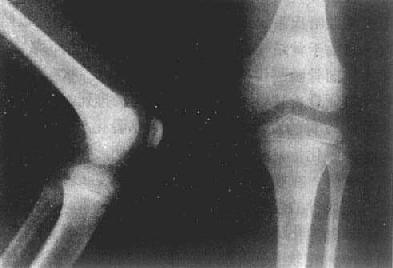

(一)小儿骨骼 长骨是软骨雏型经骨化形成的,一般有3个以上的骨化中心,一个在骨干,另外的在两端。前者为原始或一次骨化中心,后者为继发或二次骨化中心。原始骨化中心在胚胎第5周后在骨干中央发生,骨化迅速进行。出生时,长骨骨干已大部骨化,只两端仍为软骨,即骺软骨(epiphyseal cartilage)。因此,小儿长骨的主要特点是骺软骨,且未完全骨化。可分为骨干(diaphysis)、干骺端(metaphysis)、骺(epiphysis)及骺板(epiphyseal plate)等部分(图2-1-1、2)。

图2-1-2 儿童正常膝关节

(三)成年骨骼 成年骨骼的外形与小儿骨骼相似,但骨发育完全。骼与干骺端结合,骺线消失。只有骨干和由骨松质构成的骨端。骨端有一薄层壳状骨板为骨性关节面。表层光滑。其外方覆盖的一层软骨,即关节软骨,X线上不能显示(图2-1-3)。成年长骨骨皮质较厚,密度高。骨端各部位所承受重力、肌肉张力以及功能活动不同,其骨小梁分布的比例和排列方向也不同。此外,靠近关节附近,还常有光滑的子骨附于骨骼附近的肌腱中。位置与数目正常有所差异。以手及足部为多见。

X线上,由于软骨、关节囊都是软组织密度,不能显示,所以,相对骨端之骨性关节面间呈半透明间隙,称之为关节间隙(joint space)。因此,X线所见关节间隙包括了关节软骨及其间的真正微小间隙和少量滑液。两个相对骨端的骨性关节面光滑整齐,相距匀称,间隙清晰,宽度均匀(图2-1-4)。关节间隙的宽度因部位和年龄而异。

图2-1-4 正常成人膝关节

股骨下端和胫骨上端的骨性关节整齐,间隙清晰,宽度均匀